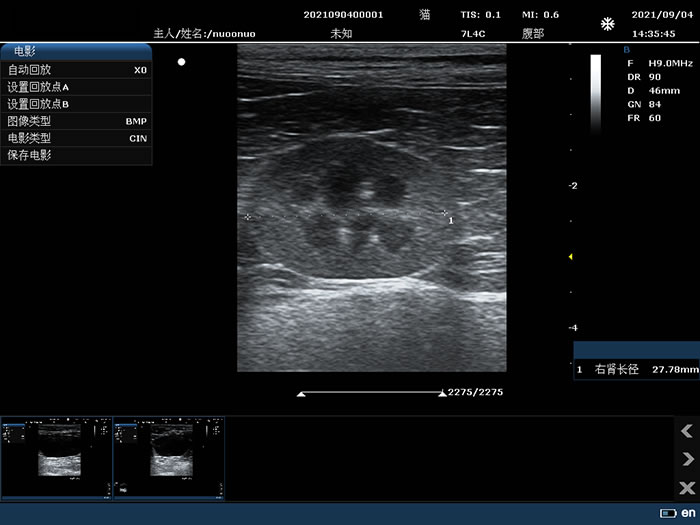

7L4C: 7.5MHz/L38mm/128,Convex array probe

Kidney

7L4C: 7.5MHz/L38mm/128,Convex array probe

Kidney